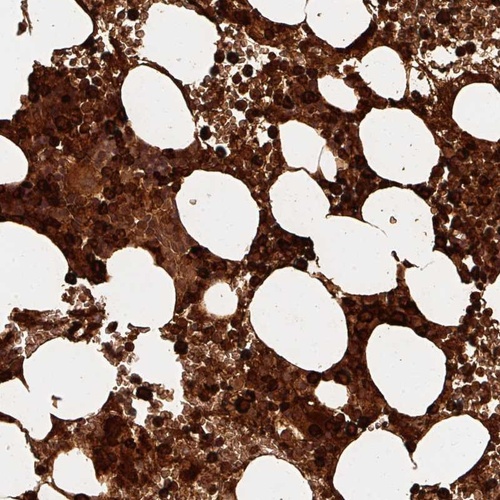

Immunohistochemical staining of human bone marrow shows strong cytoplasmic positivity in hematopoietic cells.